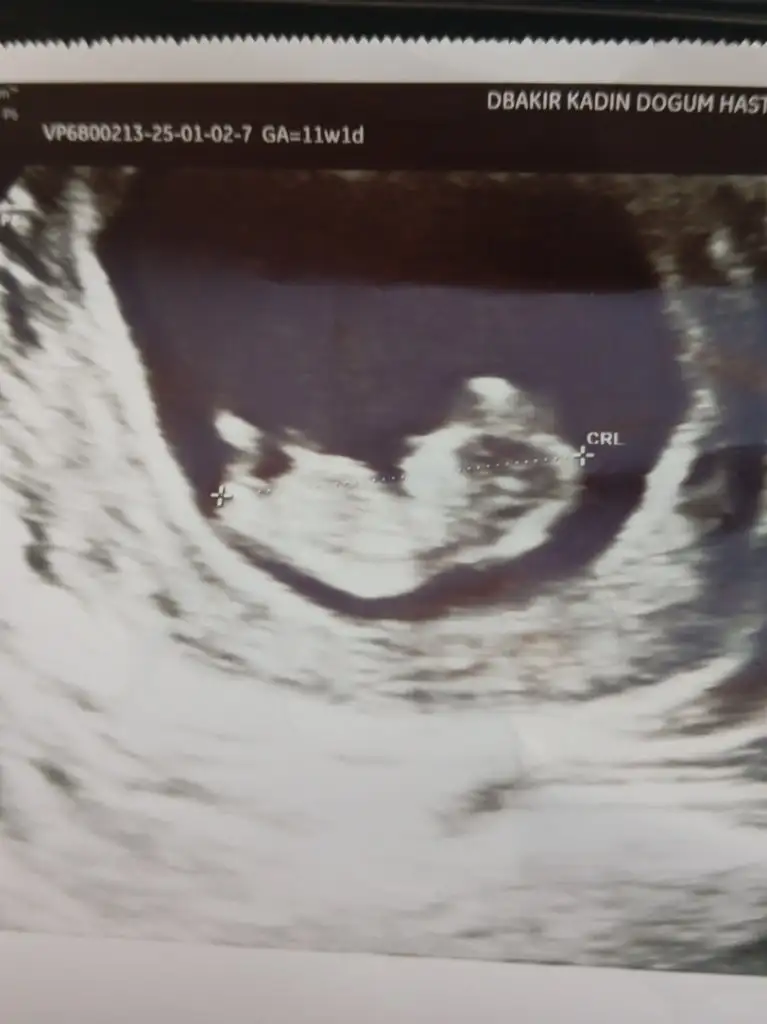

Merhaba benim bebeğimi de tahmin edermisiniz

Sata göre 11 haftalık

• 1000023488.webp

1000023488.webp

21,3 KB · Görüntüleme: 94